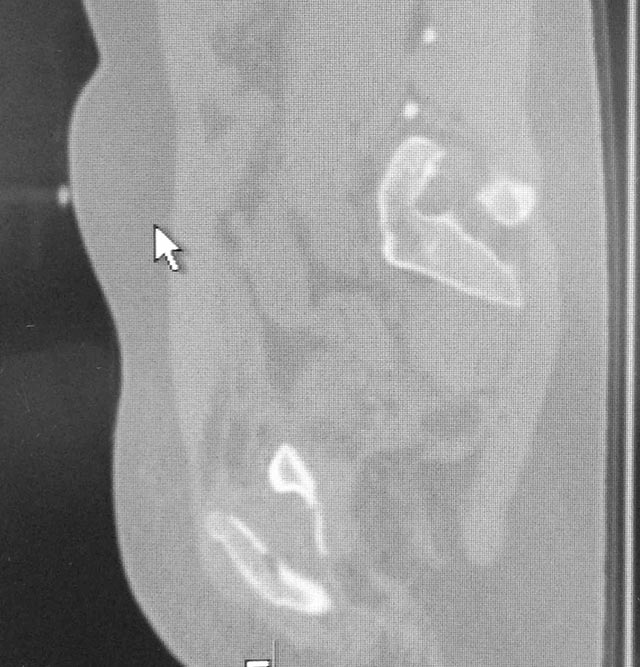

Женщина,21, социальна, без вредных превычек, сбита авто.

Кожа не повреждена. Других повреждений нет. Гемодинамически стабильна. травме 2 сут. Планируем спереди открыто через Stoppa, далее сзади крестец и ость закрыто (крестец может через обе массы?). Интересует мнение по альтернативным вариантам и по предложенному (tricks and shots). Заранее благодарен.

PS Только часть скринов с body scan, один с контрастированием пузыря.